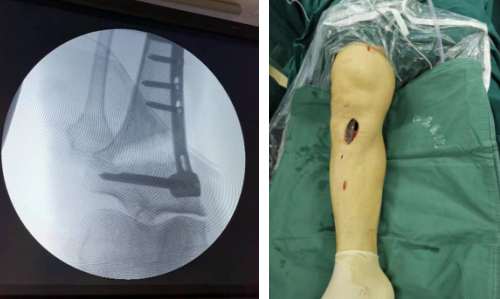

关节镜下探查清理

骨科机器人精准定位截骨

第二天,张传开主任郝亮闫成尚医生团队为患者进行了关节镜探查+机器人辅助下胫骨截骨术。术中,医生镜下探查,可见右膝关节滑膜充血水肿变性,内侧半月板撕裂严重,右股骨内髁软骨剥脱,针对镜下探查情况,予以病变半月板清除,剥脱软骨清理及滑膜切除术。随后,在骨科机器人的精准定位下进行截骨,很大程度减少软组织和骨组织的损伤,患者出血少、创伤小,术后膝关节功能的康复将更快,患者感受也会更好。